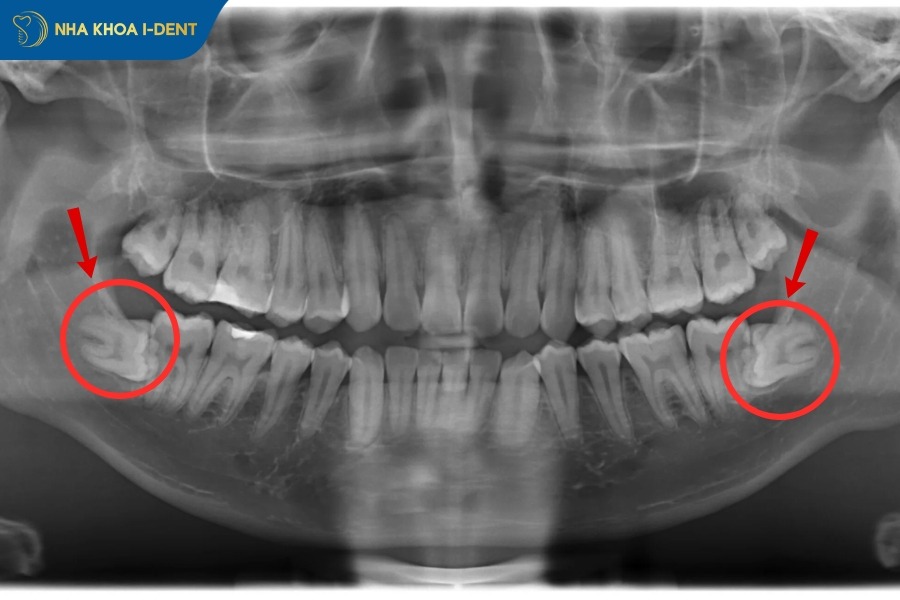

1.1 Răng khôn mọc nằm ngang, lệch ra đâm vào má

Trường hợp răng khôn mọc lệch, đâm thẳng vào má hay các răng kề cạnh, hoặc răng mọc nằm ngang một góc 90 độ bắt buộc phải nhổ răng khi niềng. Do răng khôn mọc lệch hoặc nằm ngang sẽ có xu hướng đâm trực tiếp vào răng số 7 và tạo áp lực liên tục lên các răng bên cạnh, gây đau nhức, viêm nướu, sâu răng số 7 cho nên cần nhổ răng số 8 để bảo vệ răng số 7.

Đặc biệt nếu răng mọc ngang 90 độ nằm hoàn toàn trong cung hàm sẽ tác động đến lực kéo của mắc cài và dây cung niềng răng, làm giảm quá hiệu quả điều trị và kéo dài thời gian niềng.

Nhổ răng khôn mọc nằm ngang, đâm vào các răng bên cạnh